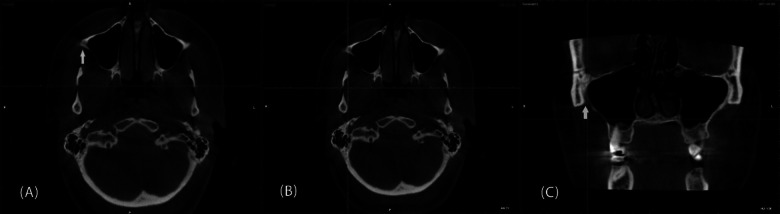

Recognizing the characteristics of the zygomatic process of the maxilla (ZPM) has several applications in implant dentistry and orthodontics. The present study evaluated the relationship between ZPM morphology, as obtained from panoramic images, and sinus pneumatization within the ZPM, according to cone-beam computed tomography (CBCT). CBCT and panoramic images of 300 patients were obtained, and the patients were divided into three age groups: Group I (15-34 years), Group II (35-55 years), and Group III (≥ 55 years). ZPM morphology was classified into J-shaped and non-J-shaped types based on panoramic images. The ZPM volume, maxillary sinus volume, and extent of sinus pneumatization within the ZPM were measured using CBCT scans, and their relationship to ZPM morphology classification was evaluated. Statistical analyses were performed using the Shapiro-Wilk test, one-way ANOVA, independent sample t-test, Mann-Whitney U test, Kruskal-Wallis test, and chi-square test (α = 0.05). Participants ranged in age from 17 to 82 years, and 67% were female. Most ZPMs were J-shaped (75%). J-shaped ZPMs had significantly greater sinus volume (1.83 ± 0.81 cm3), sinus pneumatization (53.56 ± 12.60%), and ZPM volume (3.50 ± 0.98 cm3) compared to non-J-shaped ZPMs (P < 0.05). Male participants had significantly larger ZPM volumes than females (P = 0.039). Sinus pneumatization and maxillary sinus volume were comparable across age groups and between gender. The presence of a non-J-shaped ZPM might be associated with less sinus pneumatization than J-shaped ZPMs, regardless of the patient's age or gender. Therefore, non-J-shaped ZPMs might offer more bone availability for various applications in dentistry.

Abstract Image